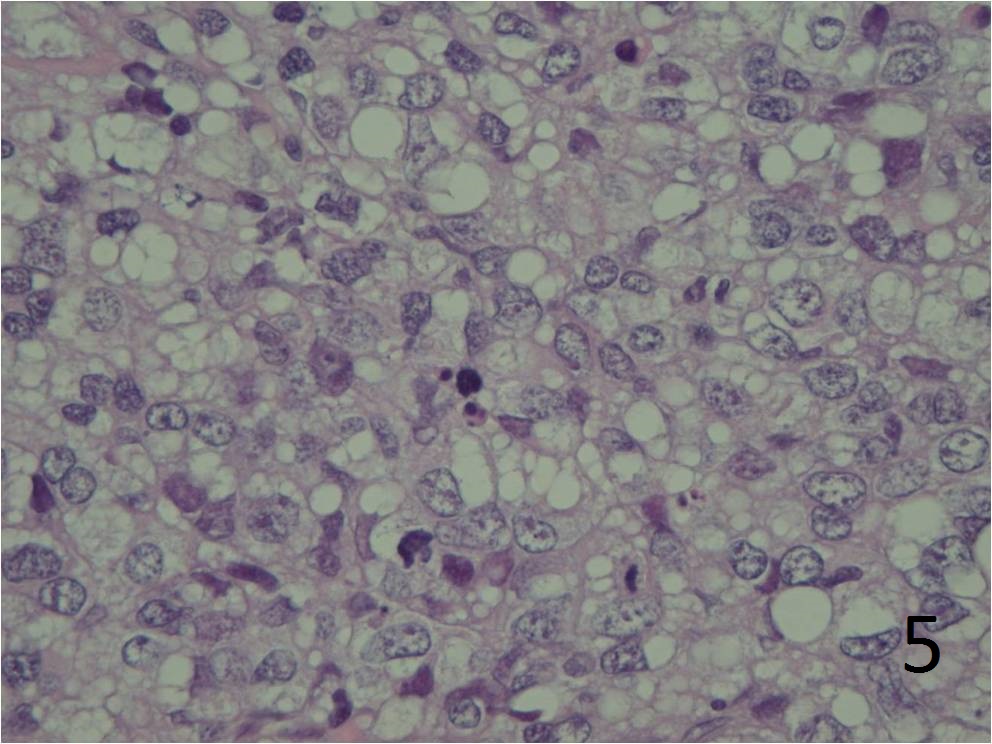

Moderately to markedly pleomorphic (Fig. 4 and 5)

Large cells and cytologically malignant

Nuclei are elongate, round or bizarre

Mitosis 10 high per field

Commonly multinucleated

Some contain identifiable lipid vacuoles

Sharply outlined

Appear empty

Indent the nucleus

No mature fat cells

Fig. 4 Microscopic: Intermediate and high (Fig. 5) power magnification show prominent pleomorphism, and many lipid vacuoles; cells are large and multinucleated. The lipoblasts are pleomorphic.